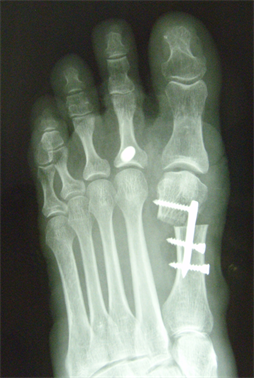

Figure 7. Patient Nr. 2. Hallux valgus with subluxed Ist MPJ and pathological DMAA.

Figure 8. Patient Nr. 2: Correction with 100% lateralization and only point contact of the osteotomy partners.

Figure 9. Patient Nr. 2. Result after 7 years. All components are corrected, no loss of lenght. Immediate full weight bearing, running after 8 weeks.